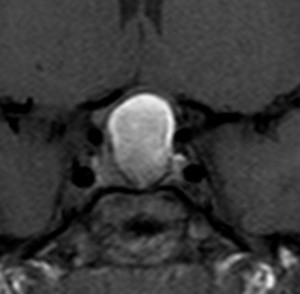

増大しても下垂体症状を出さなかった例

9歳の女の子に偶然発見された腫瘍です。何の症状もありませんでした。頭蓋咽頭腫と診断されて経過観察となりました。1年半観察しましたが腫瘍は増大して,視交差の変形が増して両耳側1/4半盲となり症候性となりました。下垂体機能は正常でした。

上のT2強調画像では,全体的に低信号で,高信号の部分が混在します。上右のCISS画像では,下垂体組織が右に変移していることが推定されます。

左がT1強調画像で高信号,右がT1ガドリニウム増強像ですが腫瘍は増強されません。正常か錐体が腫瘍の右側にくっついていて,ガドリニウム増強されています。典型的なトルコ鞍部黄色肉芽腫です。画像診断で,下垂体腺腫の腫瘍内出血とよく間違われるのですが,高信号になるのはコレステリン結晶を豊富に含むからです。ガドリニウム増強される部分がほとんどないという所見が頭蓋咽頭腫とは異なるところでしょう。